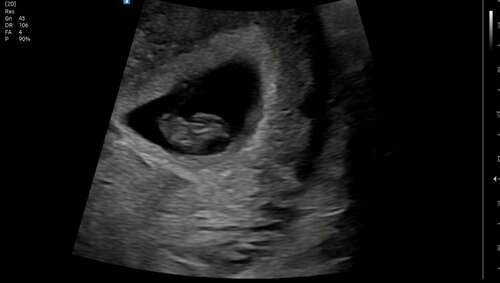

9+2 inwendig van rugaanzicht. Baby was lekker veel met zijn armpjes en beentjes aan het bewegen, zo leuk om te zien 🥰